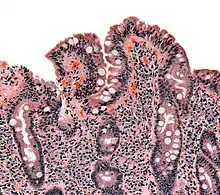

Biopsy of small bowel showing coeliac disease manifested by blunting of villi, crypt hypertrophy, and lymphocyte infiltration of crypts

Villous atrophy and malabsorption

The inflammatory process, mediated by T cells, leads to disruption of the structure and function of the small bowel's mucosal lining and causes malabsorption as it impairs the body's ability to absorb nutrients, minerals, and fat-soluble vitamins A, D, E, and K from food. Lactose intolerance may be present due to the decreased bowel surface and reduced production of lactase but typically resolves once the condition is treated.

Alternative causes of this tissue damage have been proposed and involve the release of interleukin 15 and activation of the innate immune system by a shorter gluten peptide (p31–43/49). This would trigger killing of enterocytes by lymphocytes in the epithelium.[28] The villous atrophy seen on biopsy may also be due to unrelated causes, such as tropical sprue, giardiasis and radiation enteritis. While positive serology and typical biopsy are highly suggestive of coeliac disease, lack of response to the diet may require these alternative diagnoses to be considered.[40]

The classic pathology changes of coeliac disease in the small bowel are categorised by the "Marsh classification":[99]

Marsh's classification, introduced in 1992, was subsequently modified in 1999 to six stages, where the previous stage 3 was split in three substages.[101] Further studies demonstrated that this system was not always reliable and that the changes observed in coeliac disease could be described in one of three stages:[18][102]

• A representing lymphocytic infiltration with normal villous appearance;

• B1 describing partial villous atrophy; and

• B2 describing complete villous atrophy.